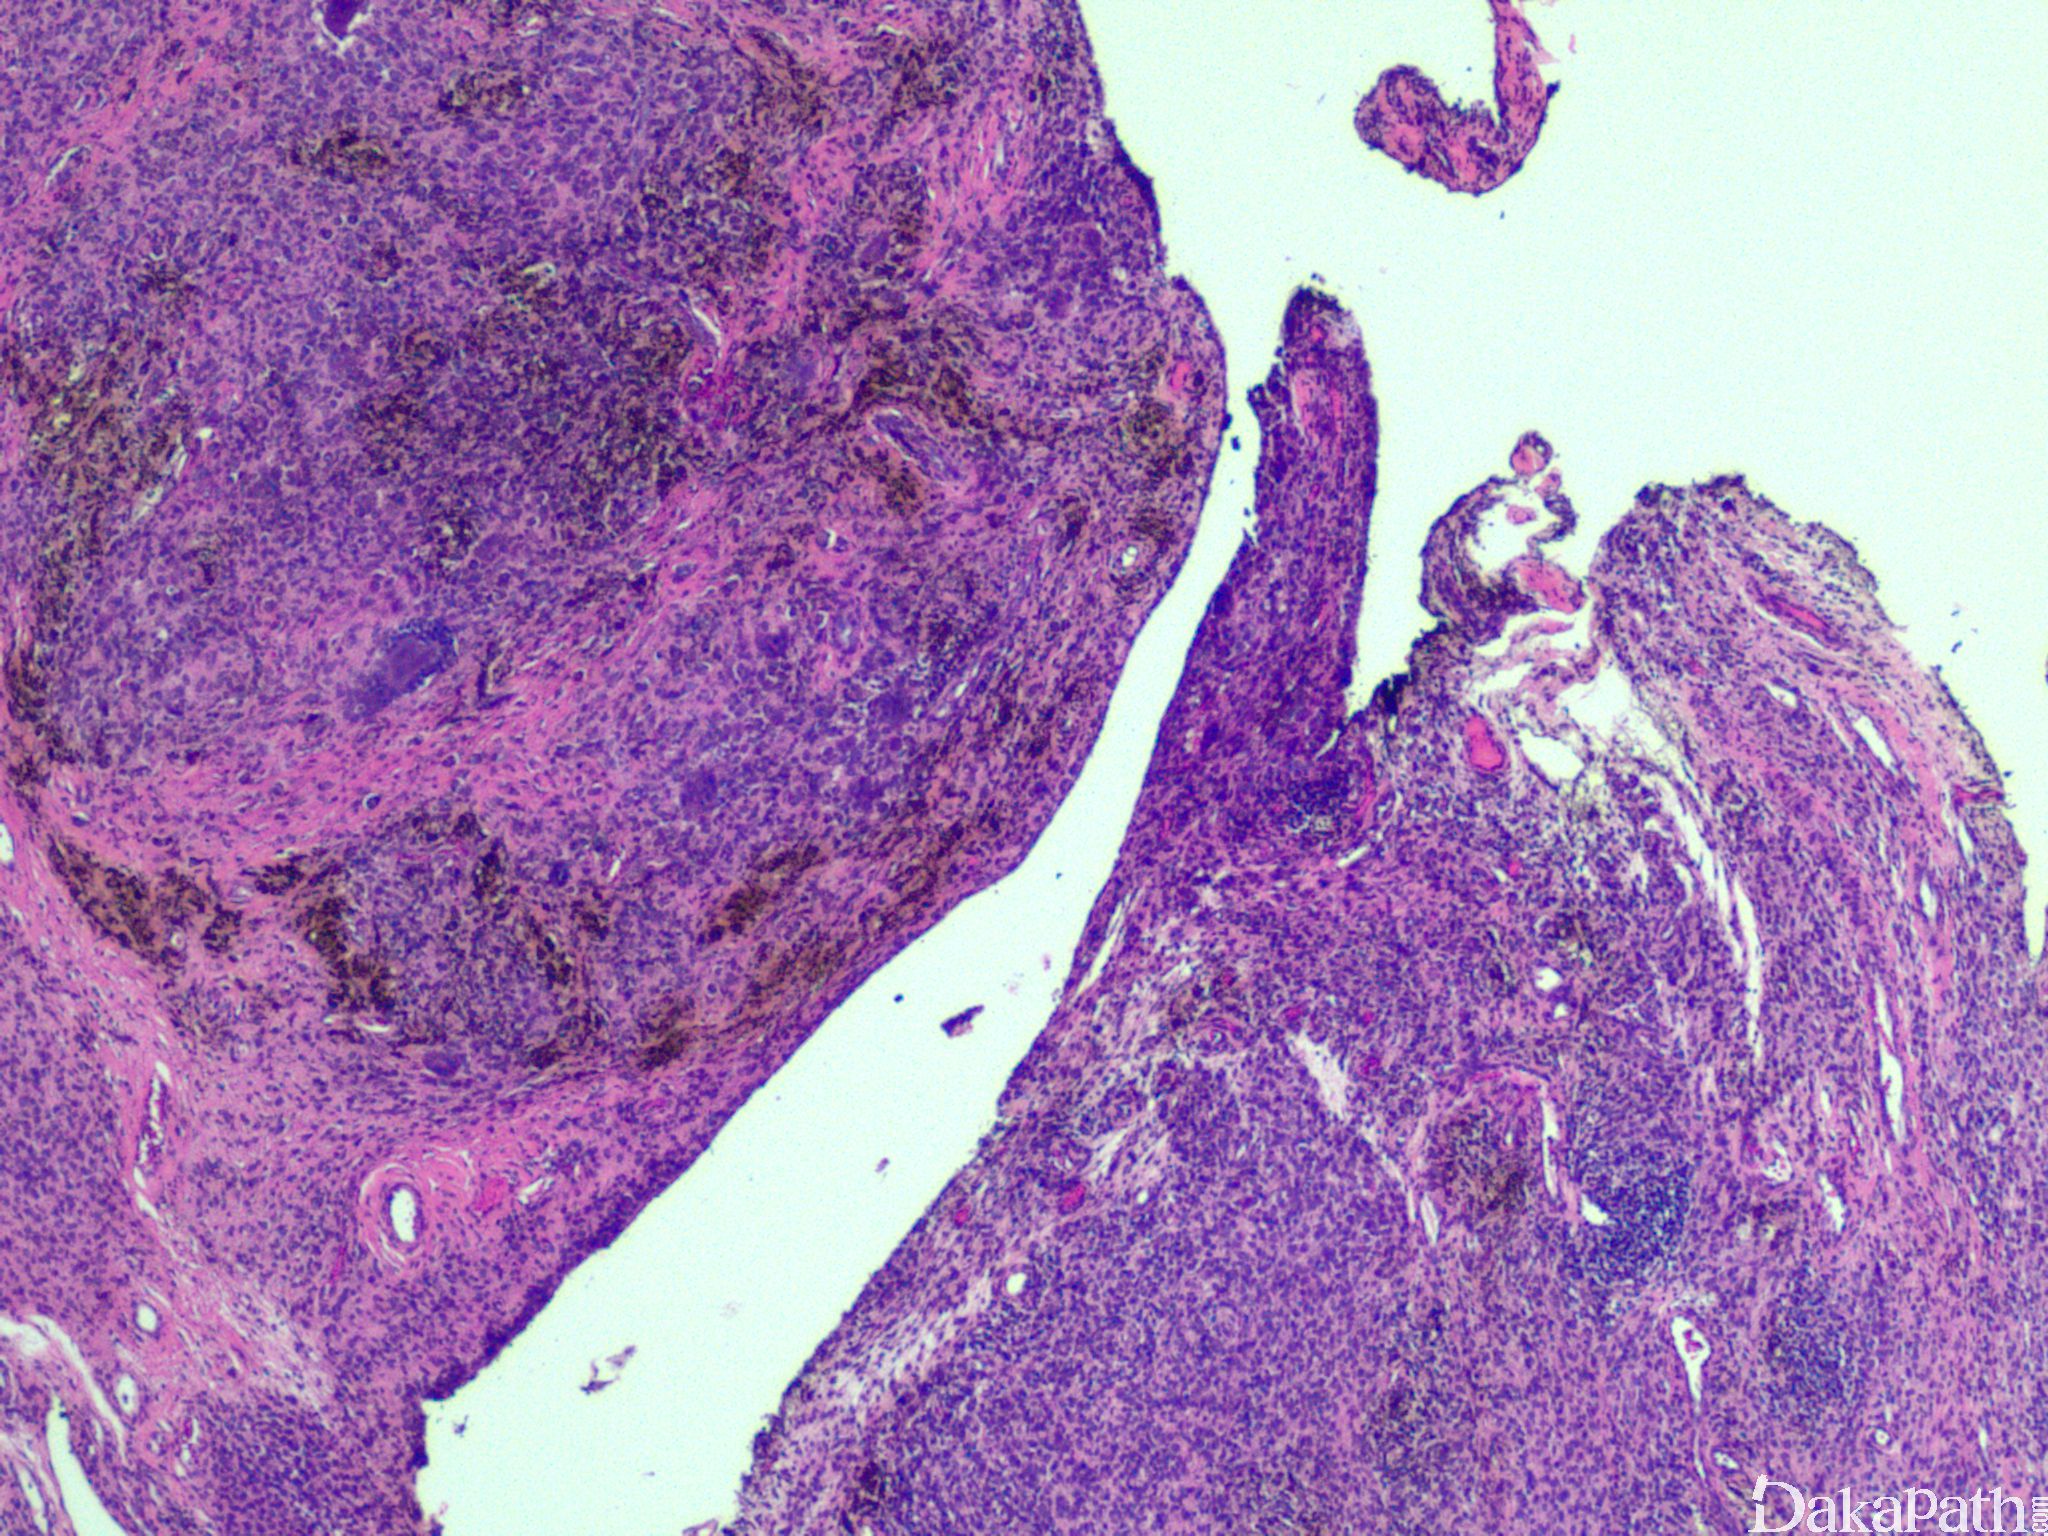

腱鞘巨细胞瘤

giant cell tumor of tendon sheathS100